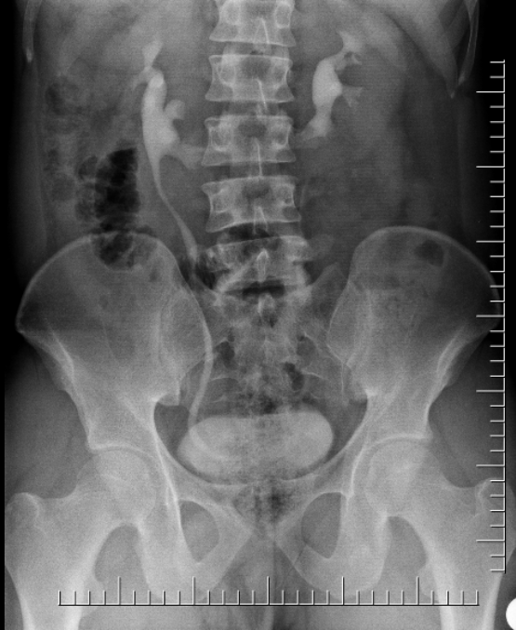

Horseshoe Kidney

Case courtesy of Dr Aditya Shetty, Radiopaedia.org. From the case rID: 27958

What are the 6 associations of this condition?